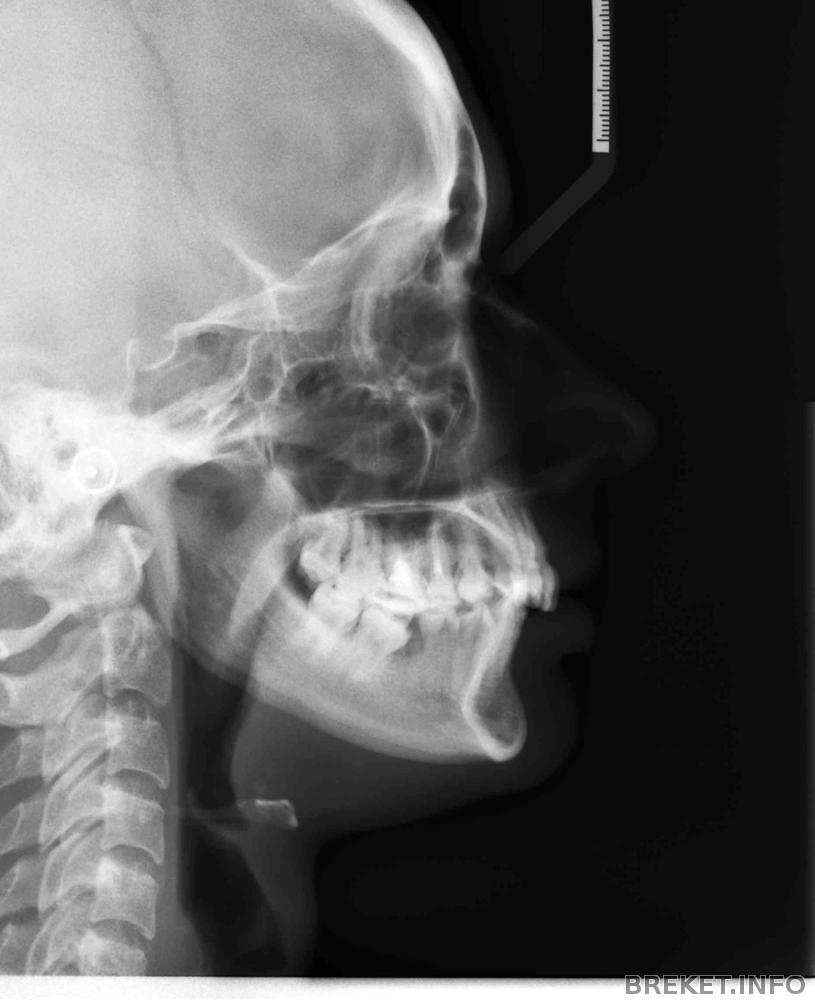

И многие не понимали и не понимают до сих пор зачем я поставила брекеты, но при рассмотрении все очень жутко

единичка заползает на другую, клыки странно повернуты, улыбка казалась "квадратной", ну и прикус не правильный, вот ТРГ